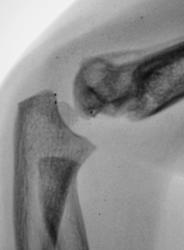

Ребенок. Снят гипс.

Первичный снимок.

3 года.

Консолидирующийся чрезмыщелковый перелом плечевой кости. Есть, конечно, угловое смещение кзади, надо было сразу репонировать, а теперь не знаю, может, для такого возраста можно и оставить.

Обычный срастающийся с допустимым смещением чрезмыщелковый перелом. Подвывихов нет.